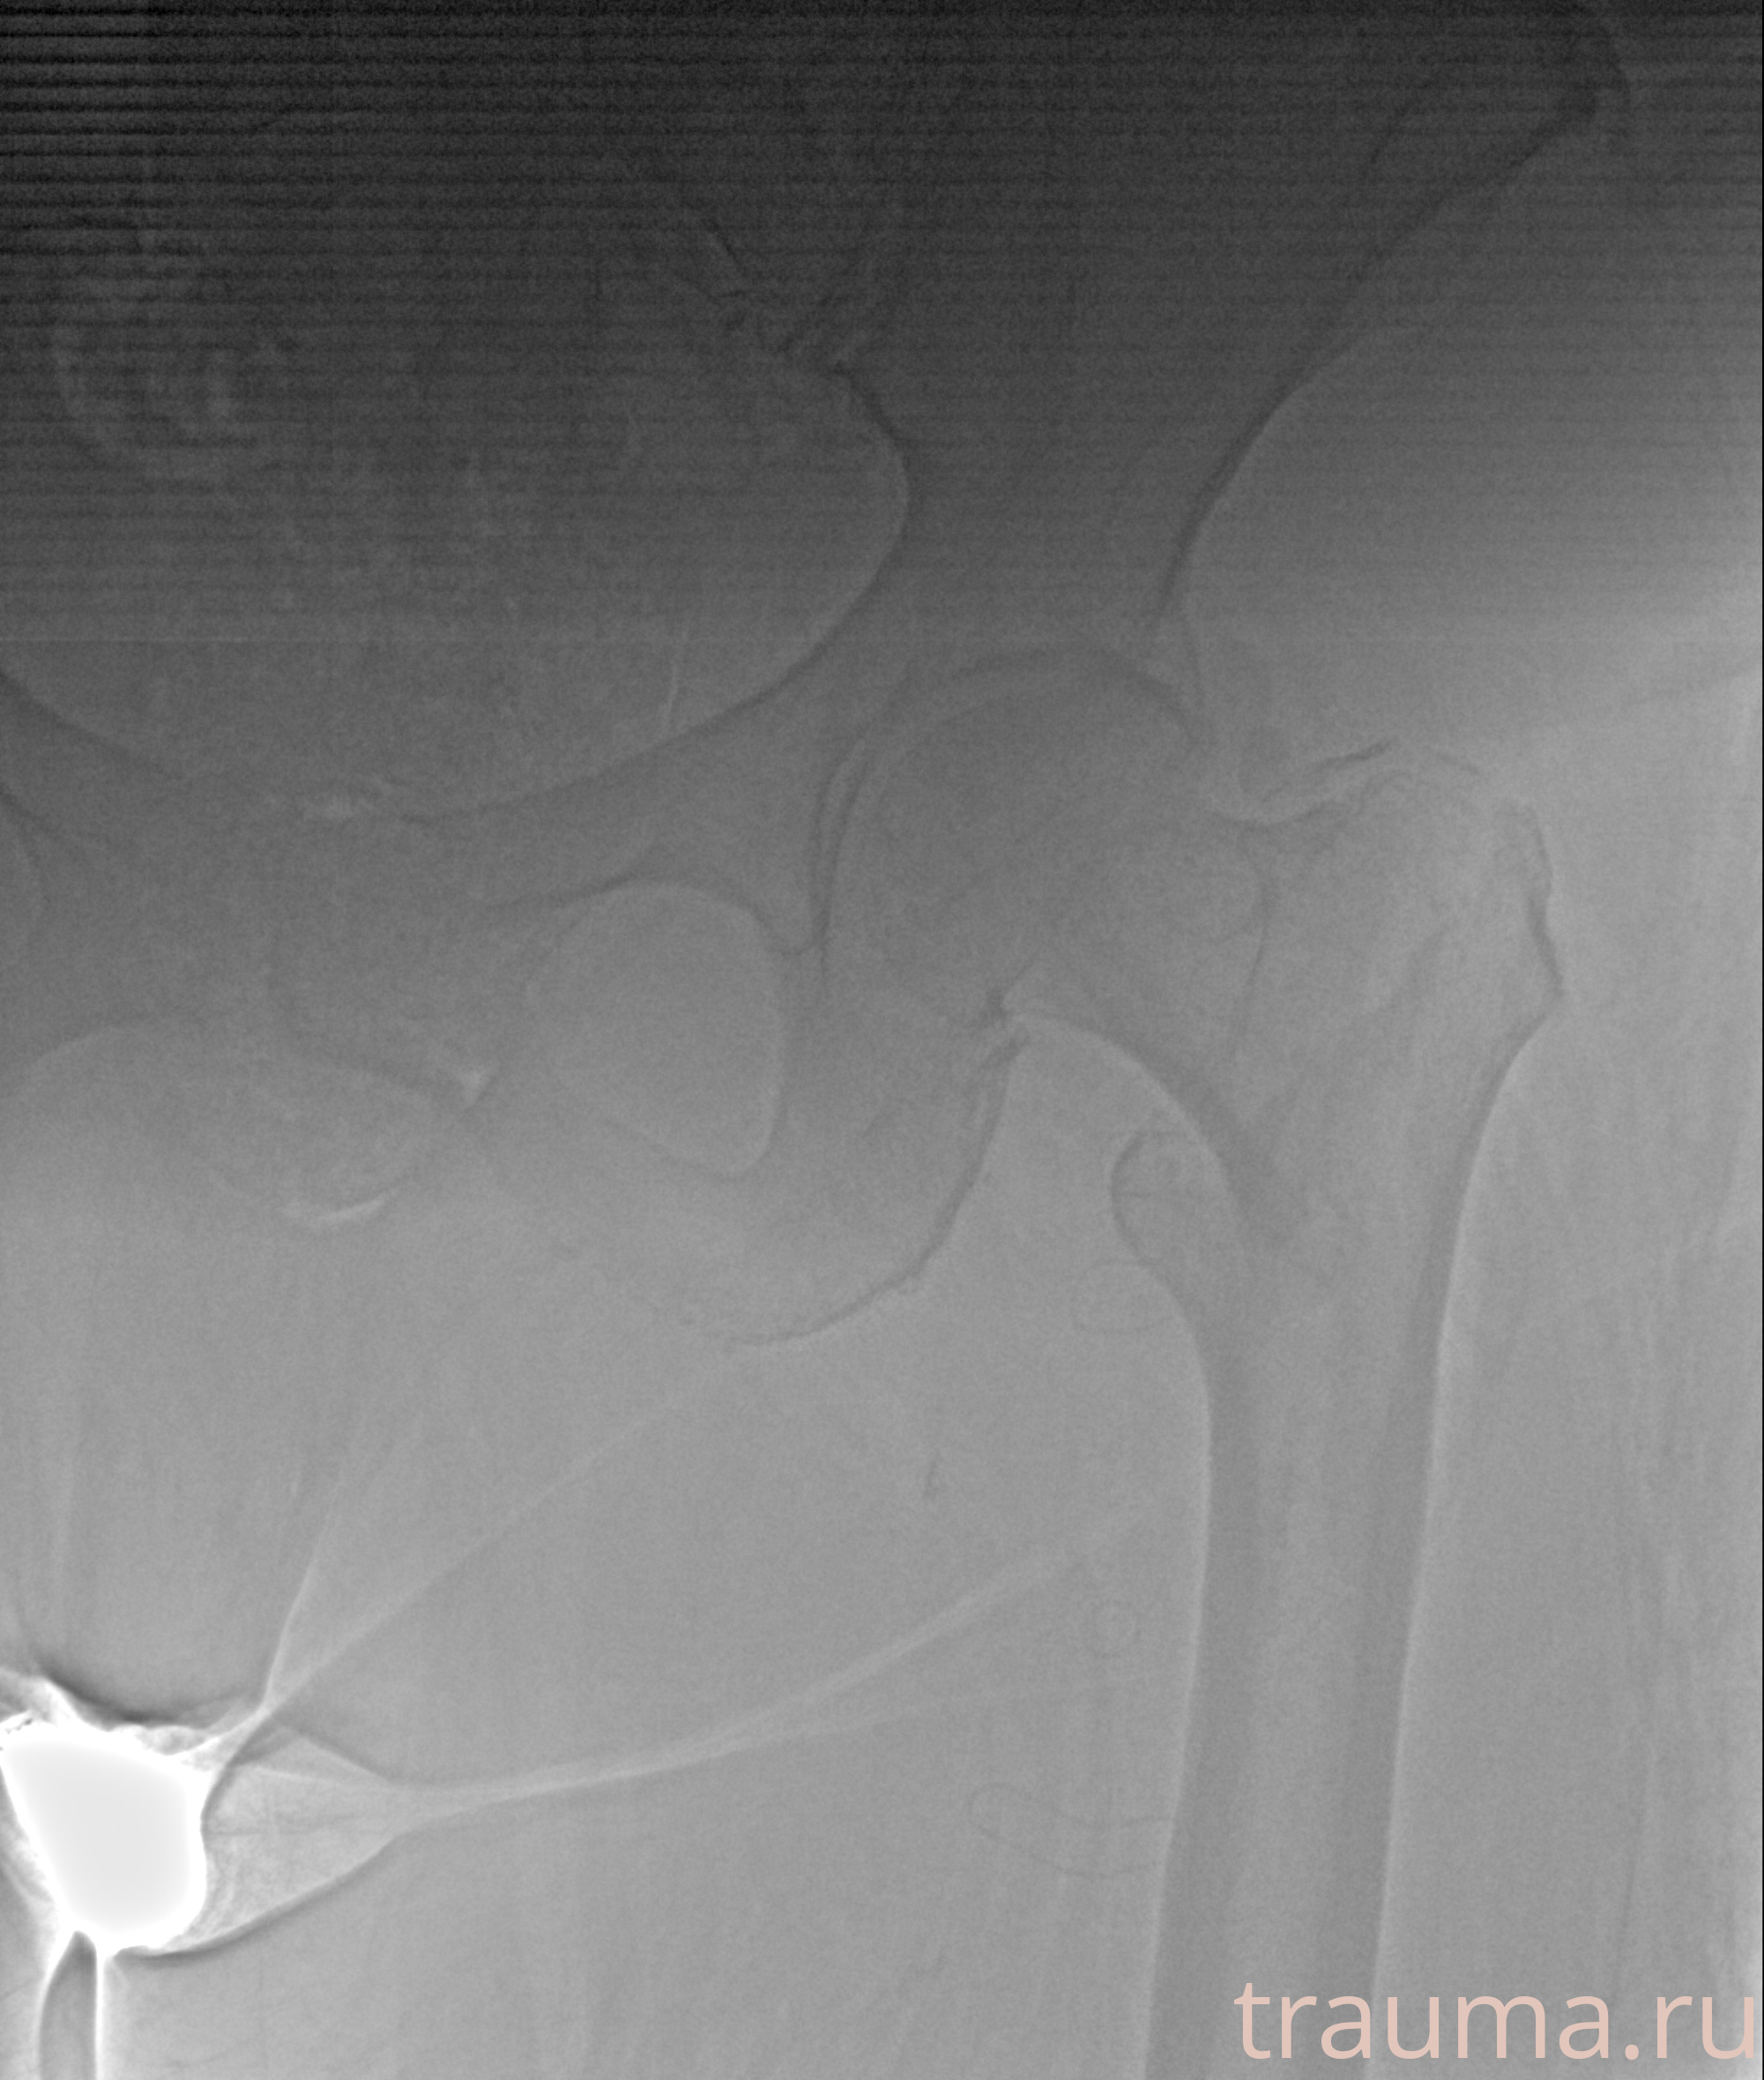

Первая помощь при переломе шейки бедра

Рентген на дому: по вашему адресу приезжает врач-рентгенолог, травматолог-ортопед с мобильным рентгеновским аппаратом, проводит диагностику травмы или заболевания, делает необходимые рентгенограммы, дает рекомендации по дальнейшему лечению. Получить качественные снимки в домашних условиях возможно благодаря уникальной методике, разработанной МосРентген Центром для института  Склифосовского